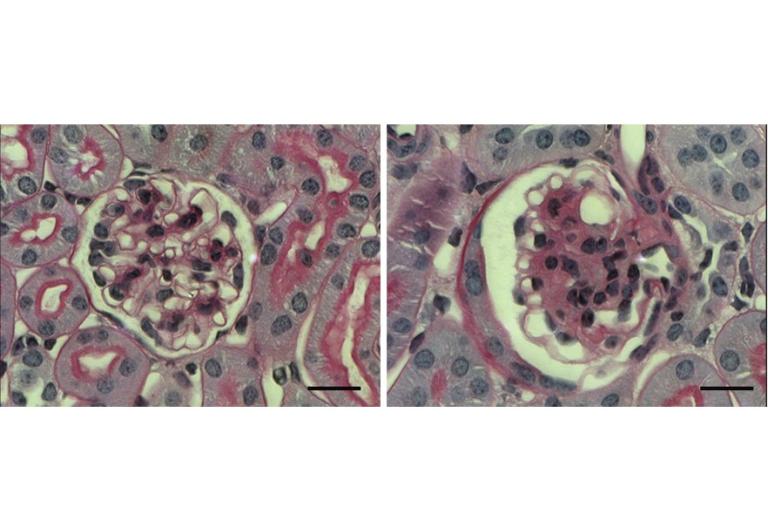

glom Left: Wild-type; Right: Nephronectin mutant glomeruli

Glomeruli are the filtration units of the kidney, containing three major cell types that function in concert to ensure the health and dynamic function of blood filtration. Defects in glomerular structure and function are a major cause of congenital and acquired kidney failure, underlying common diseases such as diabetic kidney disease. Our laboratory is studying the complex functional and structural interplay amongst these cell types in development, maintenance, and disease. One specific area of focus is the protein nephronectin and its receptor, alpha8 integrin, which are misregulated in common glomerular diseases and also a cause of congenital kidney disease.